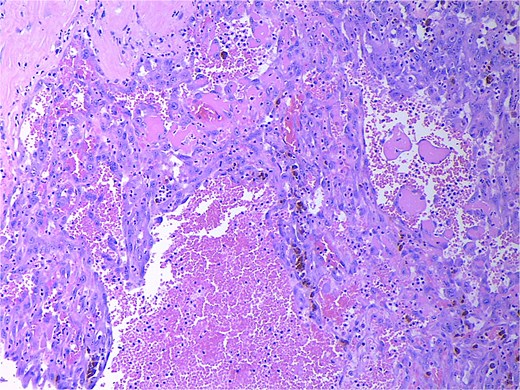

Final pathology revealed an angiosarcoma of the adrenal gland. Sections showed a predominantly hemorrhagic and necrotic mass with residual vascular forming channels within the adrenal gland (Fig. 2). Cells were pleomorphic spindled to epithelioid and atypical (Figs 3 and 4), with a mitotic count of 12/10 high-power fields. Immunohistochemistry showed positivity for ERG (Fig. 5), CD34, and focal pankeratin and negativity for SF-1, SOX10, Cathepsin-K, and chromogranin. There was no lymphatic or vascular invasion identified, and the margins were uninvolved by the tumor. The left kidney was negative for tumor, and the background adrenocortical parenchyma was benign.

Low power magnification (2×) Hematoxylin and eosin (H&E) showing the angiosarcoma within residual non-neoplastic adrenal cortical tissue. Necrosis is also present.

High power magnification (20×) H&E showing malignant cells forming vascular channels with atypia and multiple mitotic figures.

High power magnification (40×) H&E showing malignant cells forming vascular channels with atypia.

In this case, pleomorphic spindled to epithelioid cell morphology was found. In the literature, epithelioid cells were discovered most frequently with the notable exception of a small number of published cases that reported spindle cell morphology [4]. On immunohistochemistry, markers for ETS-related gene (ERG), focal pankeratin, and CD34 were positive in our case, which is consistent with the literature and further supports the diagnosis [2, 4, 8]. In addition to ACC, other differentials include metastatic carcinoma, sarcomatoid melanomas, epithelioid hemangioendothelioma, and anastomosing hemangioma [2, 9]. Therefore, morphologic findings of atypia, necrosis, and increased mitotic counts, immunohistochemical workup, and clinicoradiologic correlation are required. In this case, there were no other sites of disease, leading to the conclusion of a primary adrenal angiosarcoma.